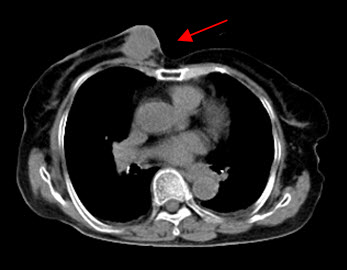

Hình 4 (a, b) cho thấy giá trị của PET/CT trong đánh giá giai đoạn của ung thư vú. Bệnh nhân Nguyễn Th. T. Tr., nữ, 63 tuổi, chẩn đoán là ung thư vú. Kết quả PET/CT toàn thân cho thấy nhiều tổn thương di căn hạch cổ, hạch trung thất, di căn 2 phổi, gan, xương tăng hấp thu FDG.

Hình 4b. Hình PET/CT ở mặt phẳng cắt ngang thấy tổn thương di căn phổi (mũi tên đỏ) và di căn gan (mũi tên da cam).